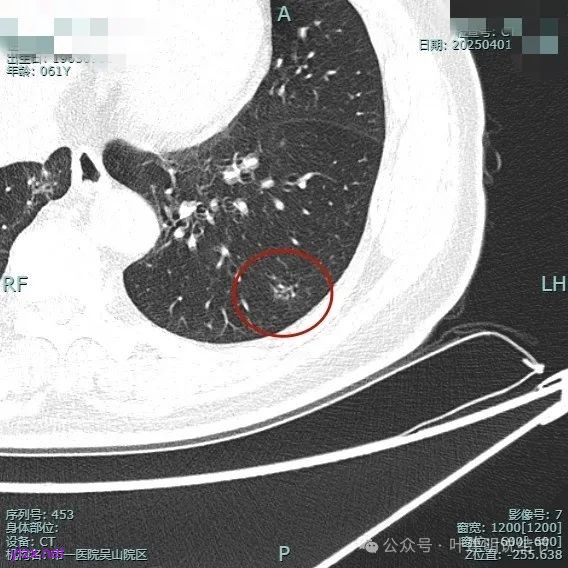

整体纵向仍偏长条些,实性部分不太致密,边上磨玻璃成分的轮廓与界限不太清楚,毛刺显得长。

仍有支气管扩张,但较2024年时密度感觉低了点。

密度较淡且缺乏收缩力。

密度杂乱,血管进入,但血管说不上明显异常增粗,磨玻璃成分淡而瘤肺界限欠清。

总体较之前密度有减低,缺乏聚拢性。

我考虑较前好转,应该是慢性炎,建议9个月后再复查。